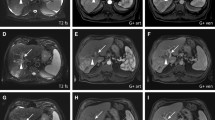

Degradable starch microspheres should be mixed with a ready-to-use solution of active substance and contrast agent. In HCC patients, DSM-TACE is performed using a mixture of 50 mg doxorubicin diluted in a saline solution with a total volume of 25 m the interval between injections to optimize the administered dose. Even if complete vascular occlusion occurs, treatment should not be discontinued, due to the risk of backflow and nontarget embolization. When DSM-TACE is performed less selectively (treatment of entire lobar or major segments), the endpoint of embolization should be a “tree-in-the-winter” appearance with occlusion of small tumor-feeding vessels but preservation of flow in the major lobar and segmental arteries. After therapy delivery, a digital subtraction angiography (DSA) is performed to confirm devascularization of target lesions and patency of the large vessels in the treated area. DSM-TACE is most effective when the procedure is performed in repeated treatment sessions. At our institution, DSM-TACE is repeated at 4- to 6-week intervals until complete disappearance of arterial enhancement is seen. In case of bilobar tumor spread in patients in whom deterioration of hepatic function is feared, the lobe with higher tumor burden is treated first, followed by the contralateral lobe. In the latter case, it is preferable to reduce the interval between the two sessions to 2 weeks if possible. Follow-up imaging is routinely performed using contrast-enhanced magnetic resonance imaging (MRI) or contrast-enhanced computed tomography (CT) in patients with contraindications to MRI.